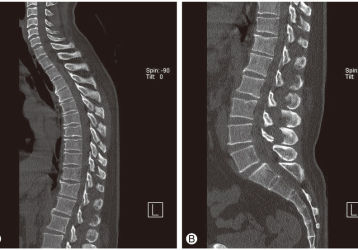

Самыми распространенными видами патологии считаются:

1. Остеохондроз поясничного отдела (встречается очень часто).

2. Остеохондроз грудного отдела.

3. Остеохондроз шейного отдела.

Патология доставляет много боли и дискомфорта. Кроме того, она может ограничить подвижность позвоночника, что ухудшает трудоспособность и нормальную жизнь человека. При первых же проявлениях представленной проблемы желательно оперативно обратиться за помощью к специалистам. Если этого не сделать, то повреждения сочленения станут необратимыми.